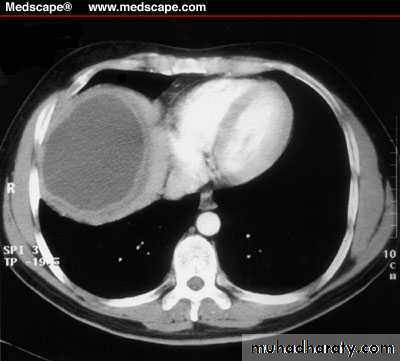

Hemangioma

Benign lesions

Malignant neoplasms: